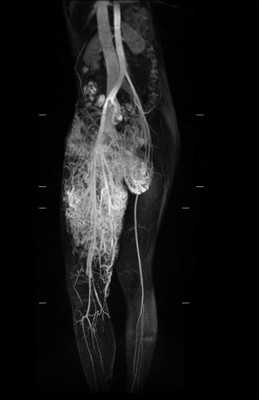

「小班克右腿的動脈與靜脈是沒有經過微血管就直接相接的『動靜脈畸形』,這是最不容易處理的狀況。」主治醫師整形暨重建外科主任李俊達表示,若要手術移除小班克的動靜脈血管畸形及微血管畸形並不容易,因為她大腿深部的動脈與靜脈連接在一起,從下腹部延伸至鼠蹊部、右大腿,加上包覆大腿皮膚表層的微血管畸形面積很大,若使用雷射方式移除,得進行十次以上的雷射手術,還可能引起大出血;另一種治療方式則是使用栓塞手術,但可能會造成皮膚潰爛或引起併發症,若要全部移除是較為困難。

經過醫療團隊仔細的評估,治療方式優先以移除影響小班克生活最大的動靜脈畸形瘤為主,李俊達主任說,先由臺大醫院影像醫學部腹部影像診斷科梁博欽主任透過血管栓塞手術減少腫瘤的血液供給量,待動靜脈血管畸形瘤因為供血量減少,開始發黑萎縮後,接著由李俊達主任、整形外科團隊及臺大醫院整形外科主任戴浩志聯手移除腫瘤,並使用超音波刀邊切除邊將血管阻塞,不僅對正常的皮膚組織傷害較小,也能降低出血量。手術順利於三小時內切除了直徑約十公分,總重兩百七十公克的腫瘤。